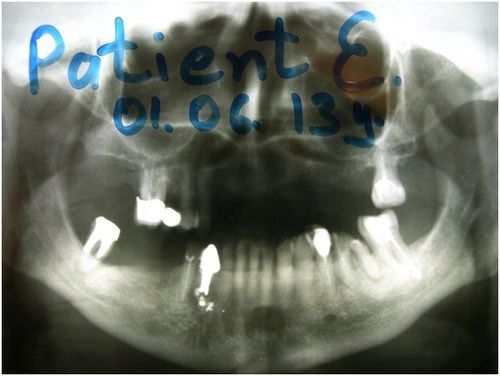

ОПГ 1. Єжова Л.В. 65 років. Кістозна порожнина під 43.

При першому зверненні в «НАНО-ДЕНТ» пацієнтці був поставлений діагноз: нагноившаяся кіста кореня 43, загострення хронічного гранулирующего періодонтиту (свищ) 43. Було прийнято рішення про консервативному лікуванні 43. Кістозна порожнину під 43 була оброблена як через кореневий канал 43, так і через свищевой хід. Корінь 43 закритий під пов'язку.

Прицільна рентгенографія 43 показала, що ГАНГ під дією гравітації локалізувався переважно на дні порожнини під 43.

ОПГ 2. Через два місяці від початку лікування порожнину під 44 зменшилася в розмірі, ГАНГ інтегрує з навколишнього порожнину кісткою. 43 запротезірован внутрішньокореневого культевой срібною вкладкою для подальшої фіксації на вкладку металокераміки.